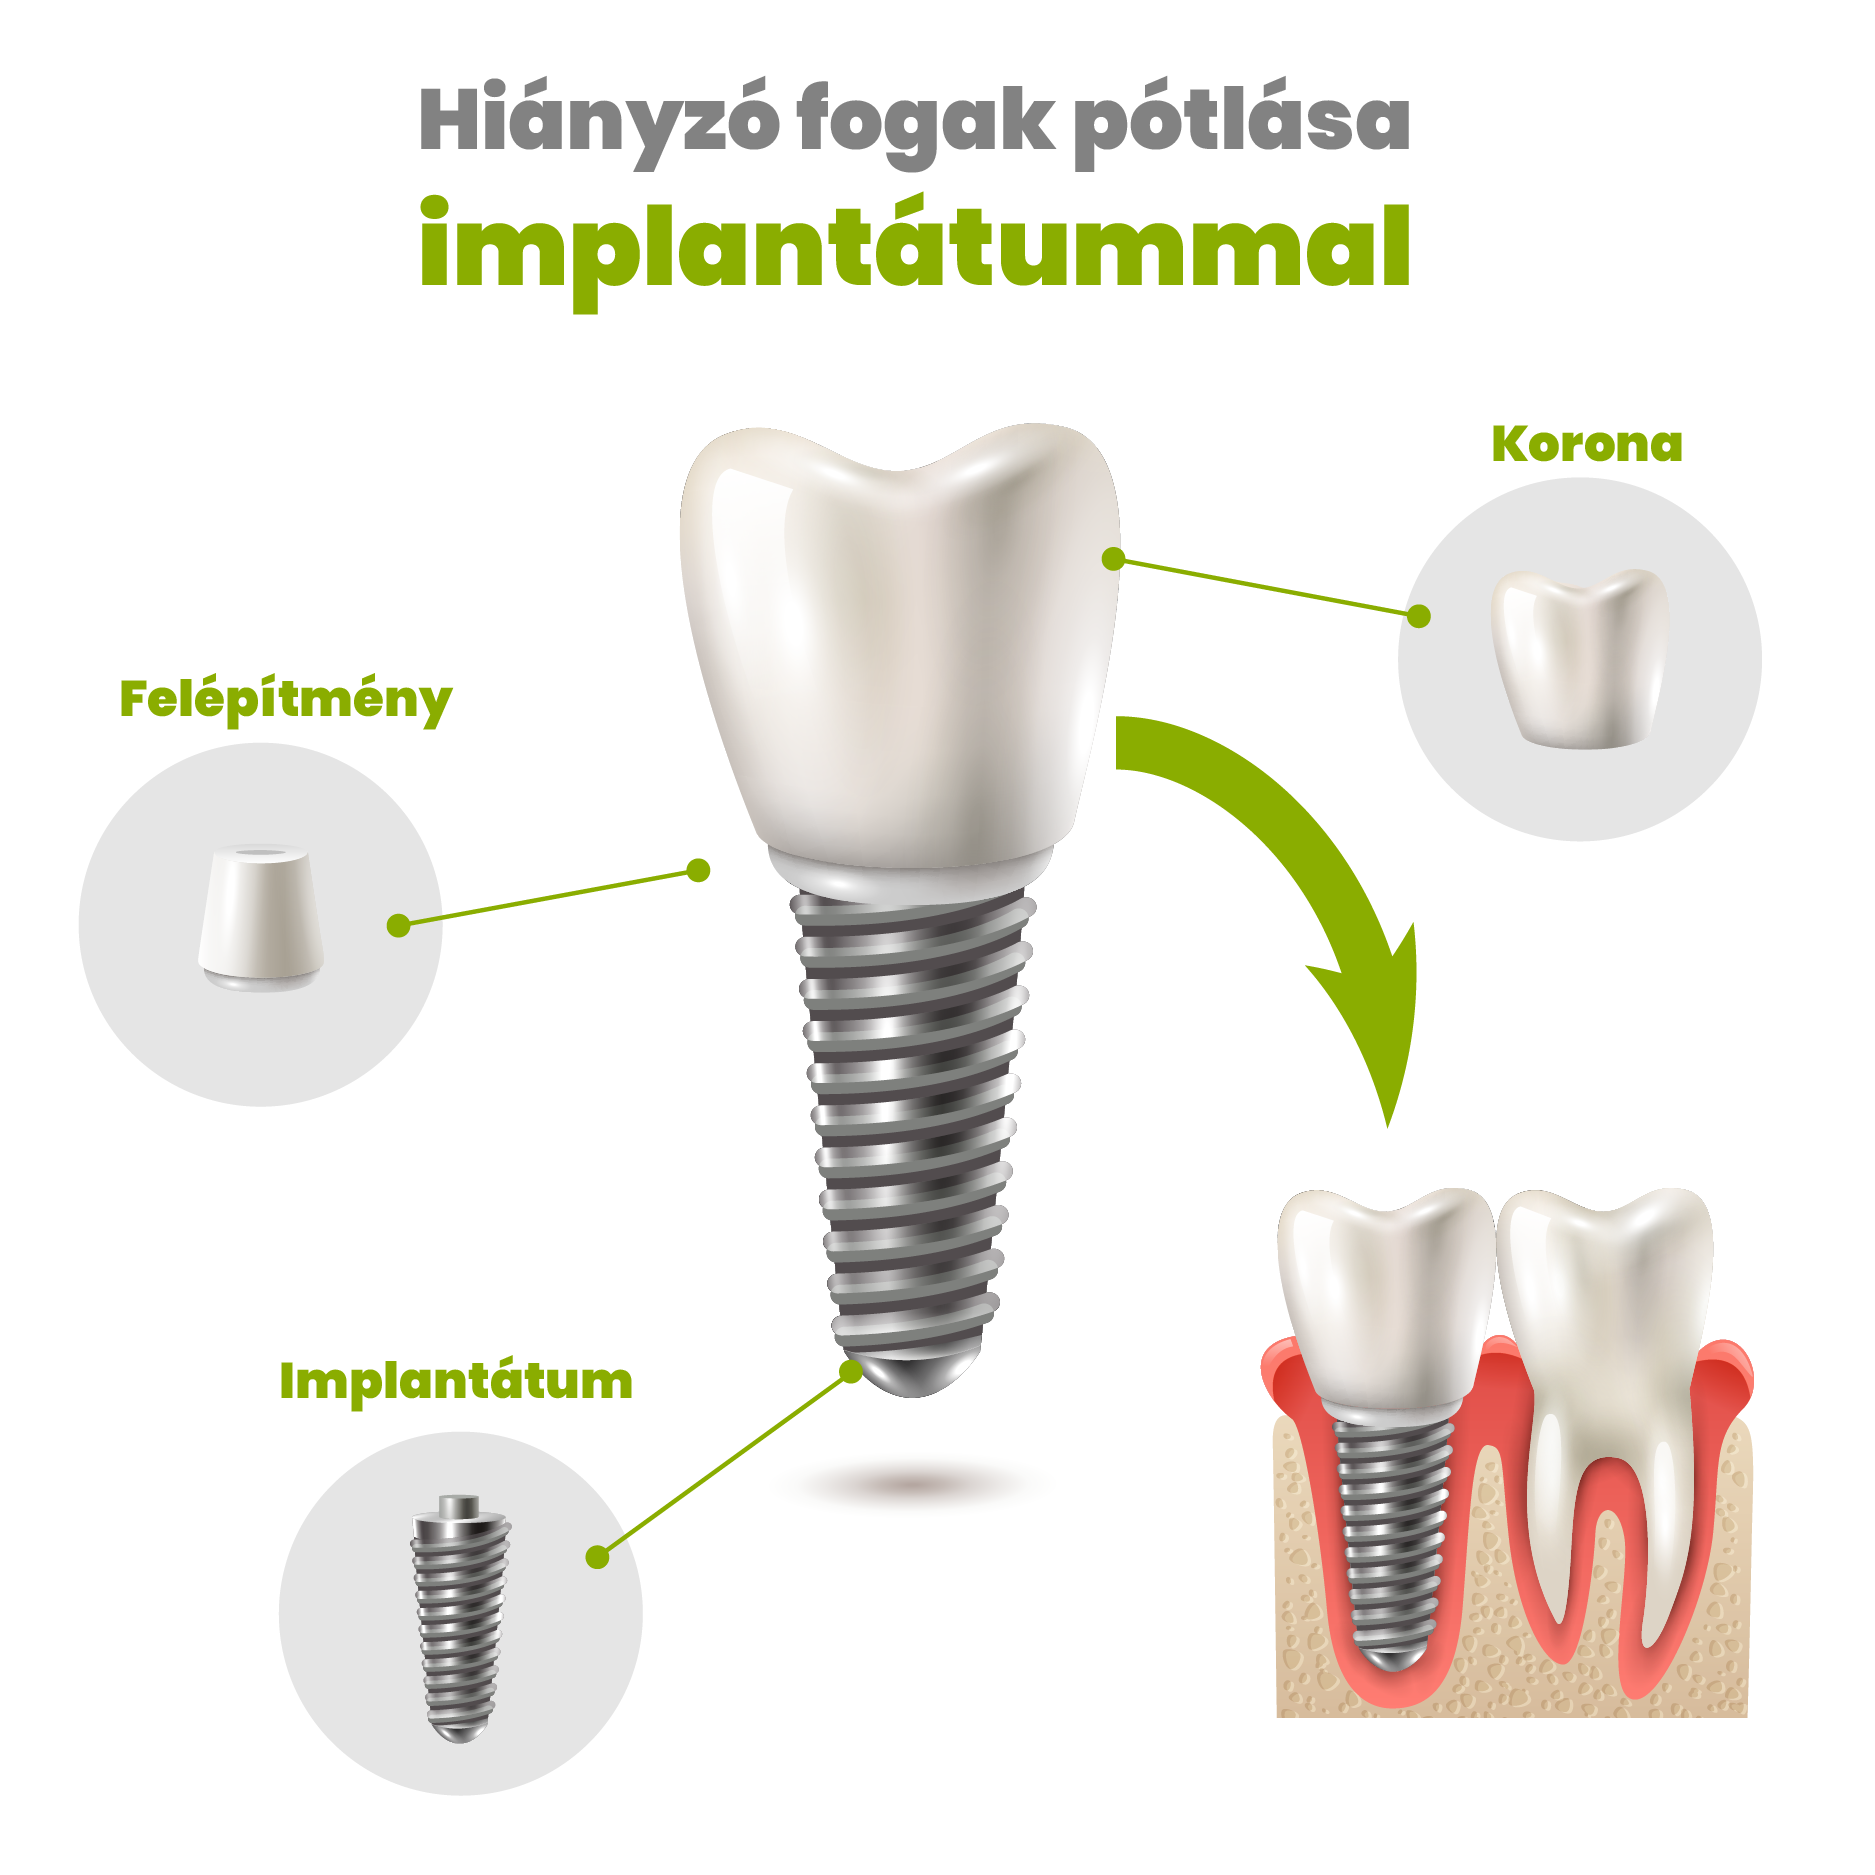

What is an implant?

An implant is an artificial root that is used for replacing the root of the missing tooth. It is placed under the gum, into the jawbone by a simple surgery, under local anesthesia. After the healing period, which is approximately takes 4-6 months, a connecting abutment and a crown is placed on top.

The implant forms a biological connection with the surrounding bones, this makes it an utterly stable base for a crown, a bridge or even a complete denture.